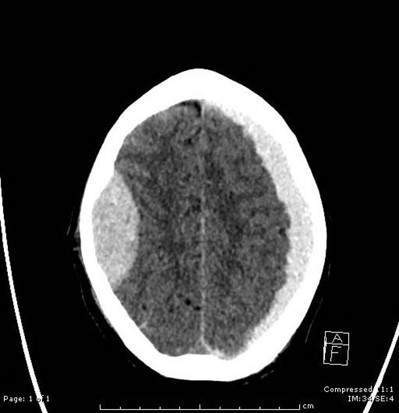

The CT head shows all of the following, except?

a) Effacement of sulci (sign of high ICP)

b) Subdural hematoma

c) Midline shift

d) Epidural hematoma

A